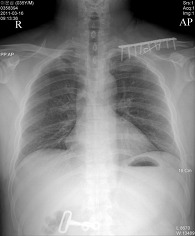

*Chest AP(흉부전후방향촬영법)

검사목적

환자의 상태가 Erect에서는 검사를 할 수 없을 때 시행하며, 폐병소의 검사에 있어서 보충적인 촬영으로도 시행된다.

Central Ray

T-6 높이에 수직으로 입사

Collimation Size

성인(14 " X 14 ", 14 " X 17 "), 소아(10 " X 12 ", 8 " X 10 ")

Position

환자는 Supine 또는 Sitting Position을 취한다. Detector의 중앙선을 흉부의 정중면과 일치시켜  놓고, Film의 상연이 양측 견부의 위 약 5cm에 놓이도록 Detector의 위치를 조정한다.

Check Point

Apex 부위가 넓게 나왔는가

Clavicle의 농도가 적당하고 hilum의 추구가 가능한가

Scapular가 폐야에서 제거되었는가

Diaphragm의 주행을 추구할 수 있는가

Breast 음영과 hilum을 구분할 수 있는가

Liver 와 lung이 중복된 부분에서 hilum을 구분할 수 있는가

Media Sternum 음영영역이 나타나고 있는가

우심실 2궁과 diaphragm의 교차상이 잘 나타나고 있는가

Clavicle이 대칭으로 잘 나타나고 있는가

Pulsation으로 인한 폐문리의 흐림이 적은가

심장과 폐가 중복되고 있는 부분의 hilum은 잘 구분할 수 있는가

costophrenic angle이 잘 나타나고 있는가

collimation이 적절한가